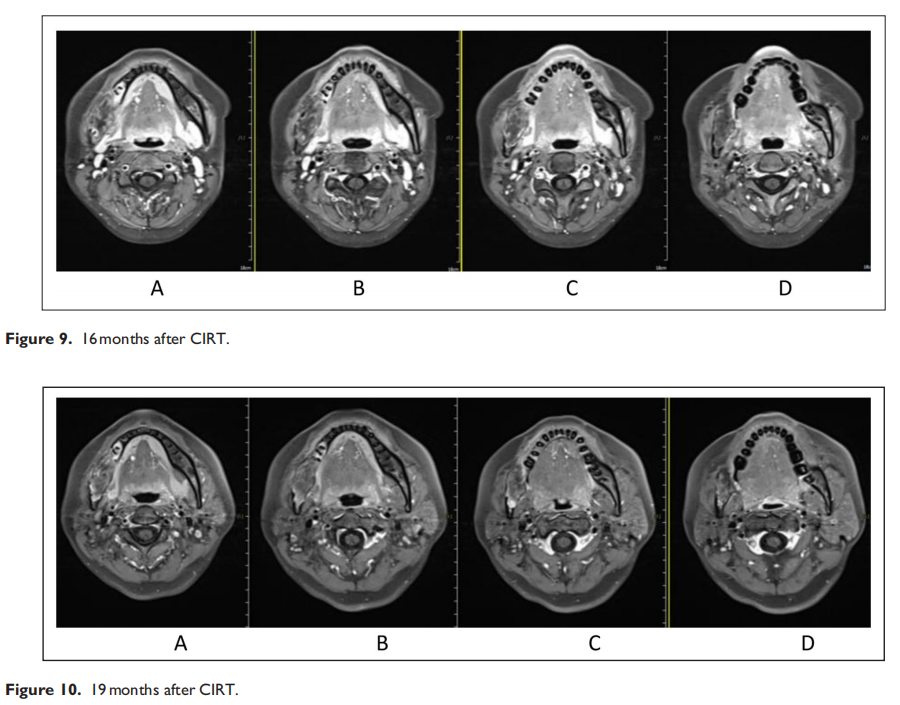

Carbon ion radiotherapy for recurrent ameloblastoma: A case report